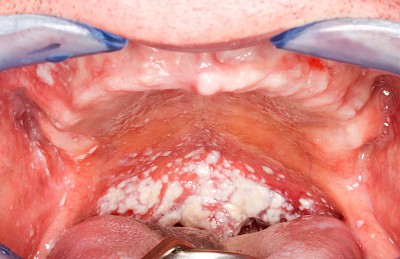

Pilzerkrankung

Pilze gehören zur physiologischen Mundflora und sind grundsätzlich nicht problematisch. Schlechte Mund- bzw. Prothesenhygiene und ggf. gleichzeitig übermäßiger Verzehr kohlenhydratreicher Nahrung kann das Pilzwachstum jedoch begünstigen Der typische Pilz im Mund ist Candida albicans, ein sprossbildender Hefepilz. Bei übermäßigem Pilzwachstum spricht man von einer Pilzerkrankung, Pilzfinfektion, Pilzbefall, Soor oder Candidose. Pilzerkrankungen können auch im Fall guter Mundhygiene auftreten bei:

Wenn die Intensivierung der Mundpflege allein den Pilzbefall nicht zu verhindern vermag, sind in manchen Fällen dann zusätzliche Maßnahmen wie Medikamente gegen Pilze (Antimykotika) nach ärztlicher Rücksprache angezeigt.

Beispiele25 Bilder